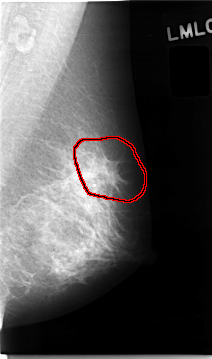

FILE: C_0026_1.LEFT_MLO.OVERLAY

TOTAL_ABNORMALITIES 1

ABNORMALITY 1

LESION_TYPE CALCIFICATION TYPE AMORPHOUS DISTRIBUTION CLUSTERED

LESION_TYPE MASS SHAPE ARCHITECTURAL_DISTORTION MARGINS SPICULATED

ASSESSMENT 4

SUBTLETY 2

PATHOLOGY MALIGNANT

TOTAL_OUTLINES 1

BOUNDARY

LEFT_MLO LINES 4656 PIXELS_PER_LINE 2752 BITS_PER_PIXEL 12 RESOLUTION 50 OVERLAY